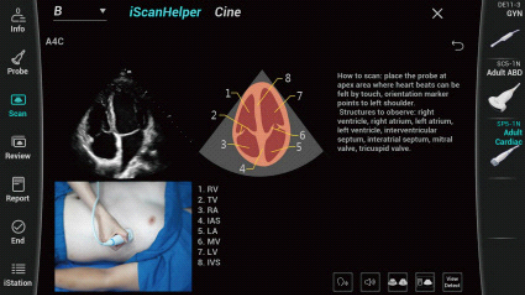

Stworzona specjalnie dla U?ytkownikÃģw z zakresu podstawowej opieki zdrowotnej, Consona wykorzystuje nowe rozwi?zania, ktÃģre efektywnie pomog? wykona? bez problemu diagnostyk? u rÃģ?nych pacjentÃģw.

Bez wzgl?du na to, czy pracujesz w szpitalu, przychodni, czy u?ywasz ultrasonografu do badaÅ ogÃģlnych, w opiece zdrowotnej kobiet lub w badaniach sercowo-naczyniowych, w serii Consona znajdziesz bardzo pot??ne narz?dzia, aby utrzyma? si? w czo?Ãģwce.

Galeria obrazÃģw